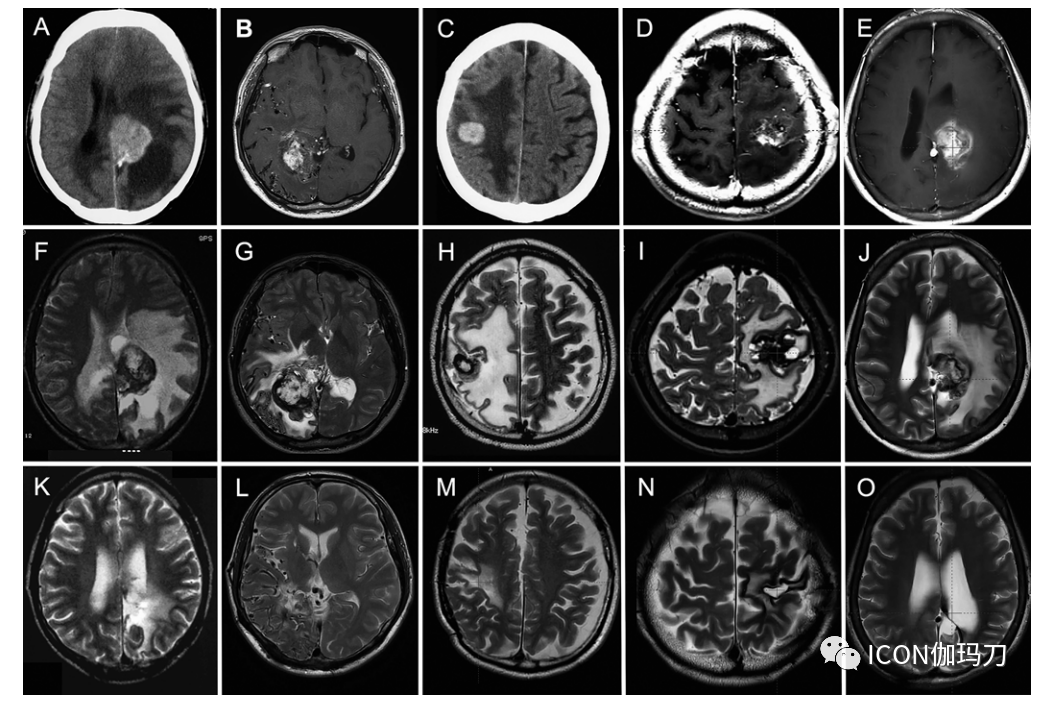

37例有肿块病变的患者中有24例在初次GKRS治疗 3.2-27.4年后出现症状,而13例患者仍然无症状(表2)。神经系统症状包括10例患者的局灶性功能障碍,6例头痛,6例新发癫痫,2例意识障碍。图1为5例典型肿块病变的神经影像学表现。MRI和/或CT显示在照射后的脑实质内或邻近有明显增强的多小叶肿块,有或没有囊肿形成。T2加权MRI显示信号强度不均匀的网状核和低强度环(图1-3)。除了强烈的焦周脑水肿外,这些神经放射学表现与普通海绵状血管畸形相似。GKRS治疗后发现肿块的中位潜伏期为10.8年(范围3.2-27.4年)。

1。病例1 (A, F, K),病例3 (B, G, L),病例5 (C, H, M),病例33 (D, I, N),病例36 (E, J, O) RFEH的典型神经放射影像学图像。A - E:增强CT扫描或T1加权MR图像显示肿块经对比剂强烈增强,有或无囊肿形成。F-J:病灶切除前T2加权MR图像,信号强度不均,边缘低信号,大面积灶周水肿。K-O:术后最后随访T2加权MR图像,无复发。